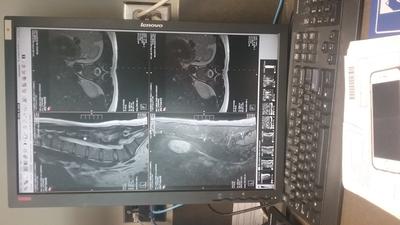

Pic of MRI of low back in October

A spine doctor ordered x-ray and MRI in October, found Spondy and a couple discs with minor protrusion. Due to significant pain, family sent me to a chiropractor at the beginning of December. I have been in twice a week, once a week, and am now waiting two weeks. The pain has decreased but still pinching and radiating down my leg to tingling in my toes from the time I stand up in the a.m.